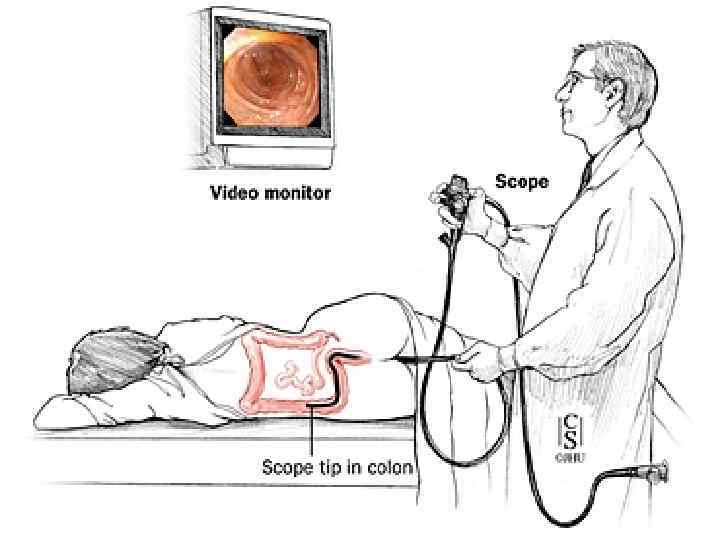

Инструментальная и лабораторная диагностика ОАК – эритроцитоз до 5 6 млн. , лейкоцитоз до 20 тыс. со сдвигом лейкоцитарной формулы влево, эозинопения. , повышение значения СОЭ. БХАК снижение уровня хлоридов с 500— 550 мг% до 400— 300 мг%, повышение остаточного азота, возможно повышение ALT AST CРБ. ОАМ – снижение количественного показателя, повышение концентрации белка. Обзорная рентгенография – наличие «кишечных арок» , «чаши Клойбера» , симптом перистости(растяжение тощей кишки). Ирригоскопия – симптом «трезубца» , видимые нарушения проходимости. Колоноскопия – визуальное определение патологии. УЗИ КТ